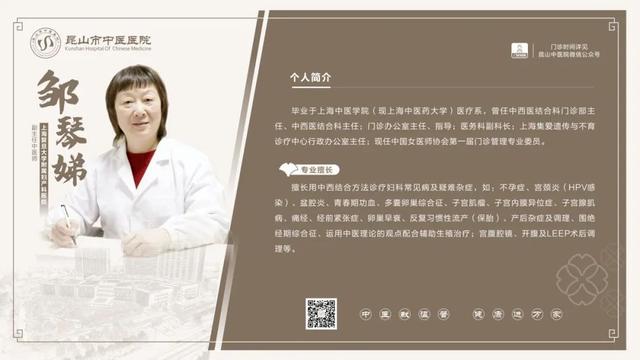

6��23��-6��29�������dz���ר�ҽ���